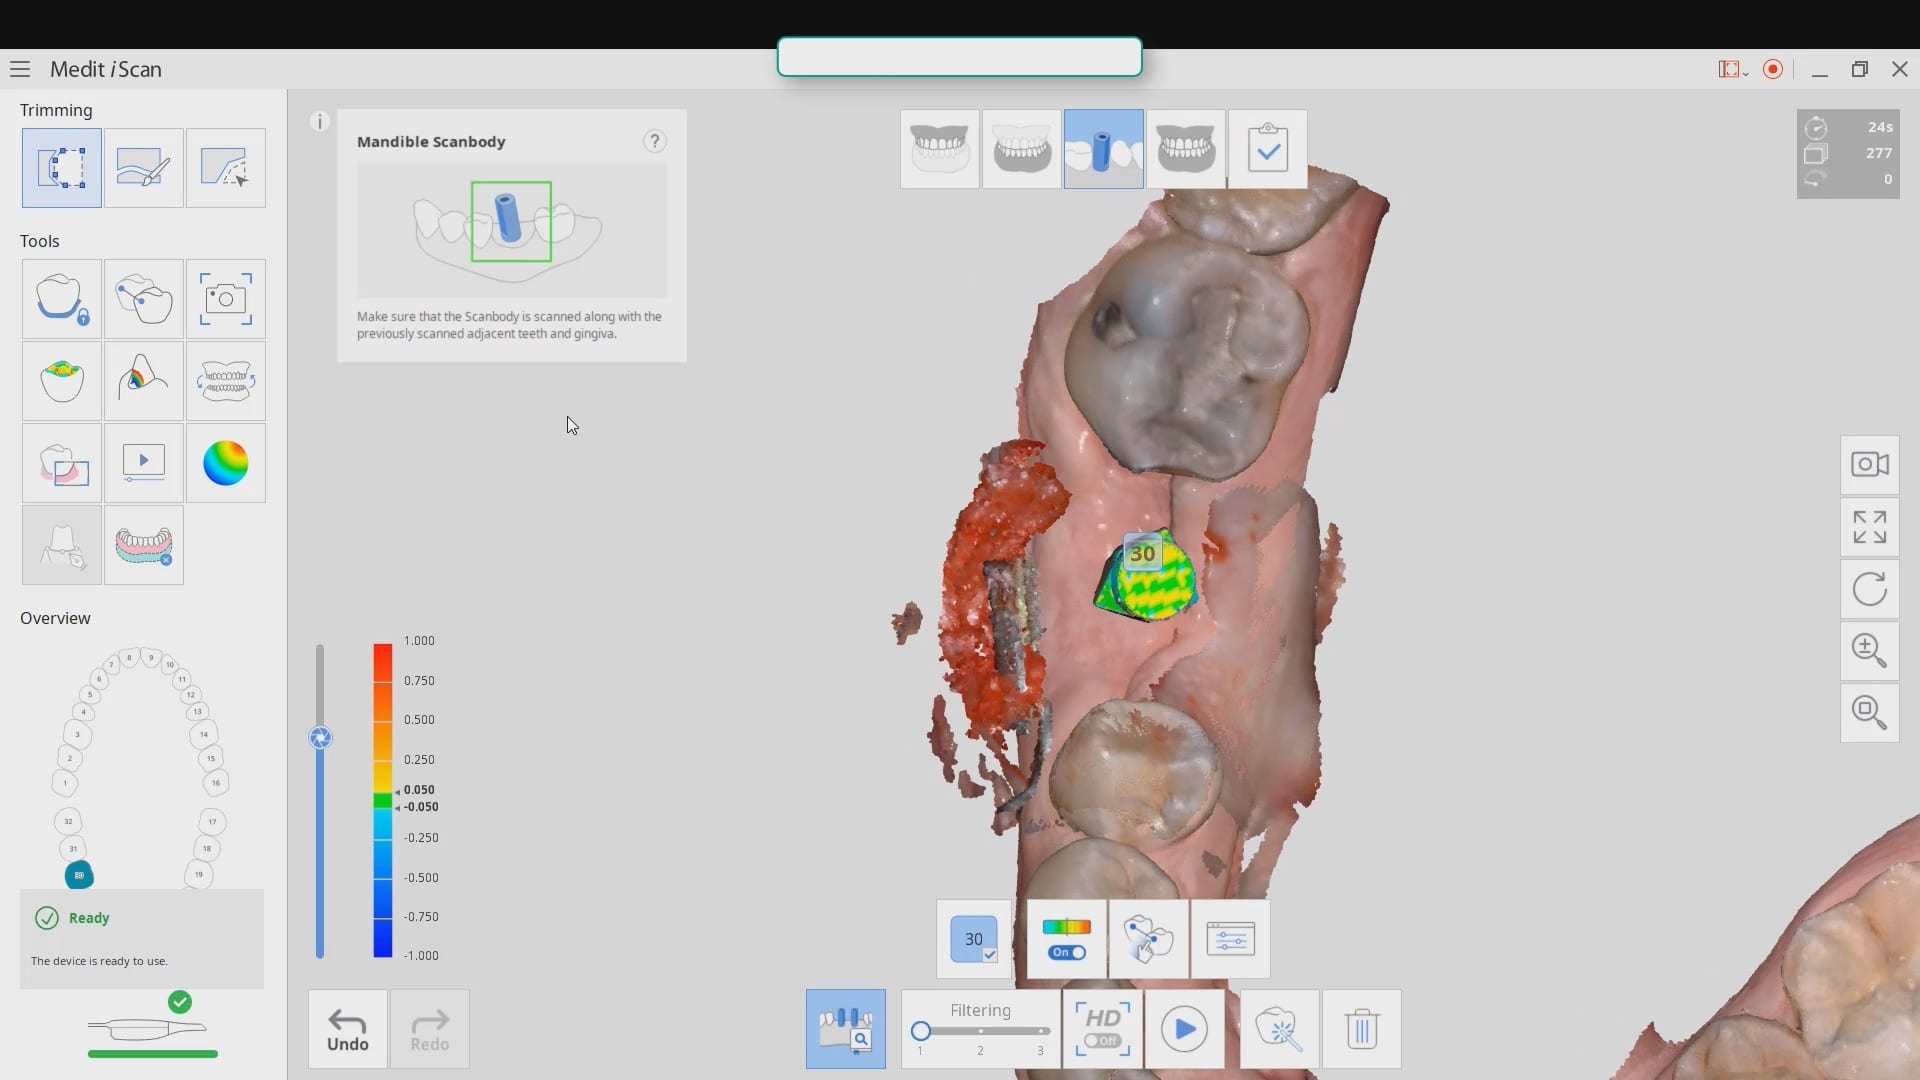

Live Intra-Oral Scan Verification Jigs for Full Arch Scans and Global Accuracy

October 25, 2019This is a detailed video demonstration that shows you how to capture full arch scans for multi unit implant cases in edentulous jaws and, more importantly, how to assess its […]